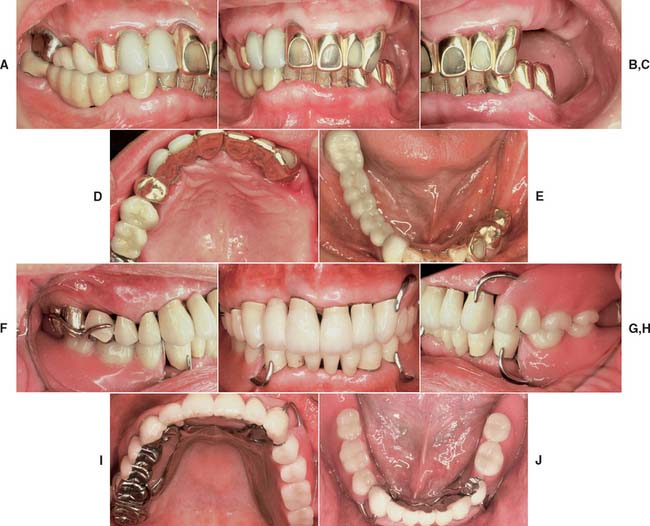

Unfortunately, periodontal disease often occurs after placement of fixed prostheses,26 especially where the cavosurface margin has been placed subgingivally27-29 or the prosthesis is overcontoured.30 Inflammation is more severe with poorly fitting restorations31 (Fig. 32-12), but even “perfect” margins have been associated with periodontitis.32 At recall appointments, particular attention is given to sulcular hemorrhage, furcation involvement, and calculus formation as early signs of periodontal disease. Improperly contoured restorations should be recontoured or replaced.

Fig. 32-12 Periodontal failure resulting from defective fixed prostheses. A, Inadequate margins and contour. B, Appearance before surgery. C, Flap reflected. D, Appearance after surgical recontouring. E, Radiograph of new cast restorations. F, Replacement restorations.

(Courtesy of Dr. C. L. Politis.)